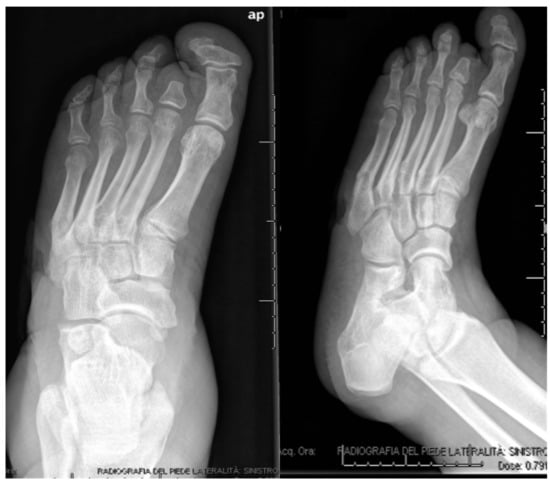

3.1. Calcaneal Lesions